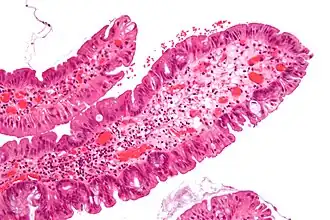

| Hyperplastic polyp | 0% | No dysplasia.[10]

|

| |

Microvesicular hyperplastic polyp. H&E stain. -